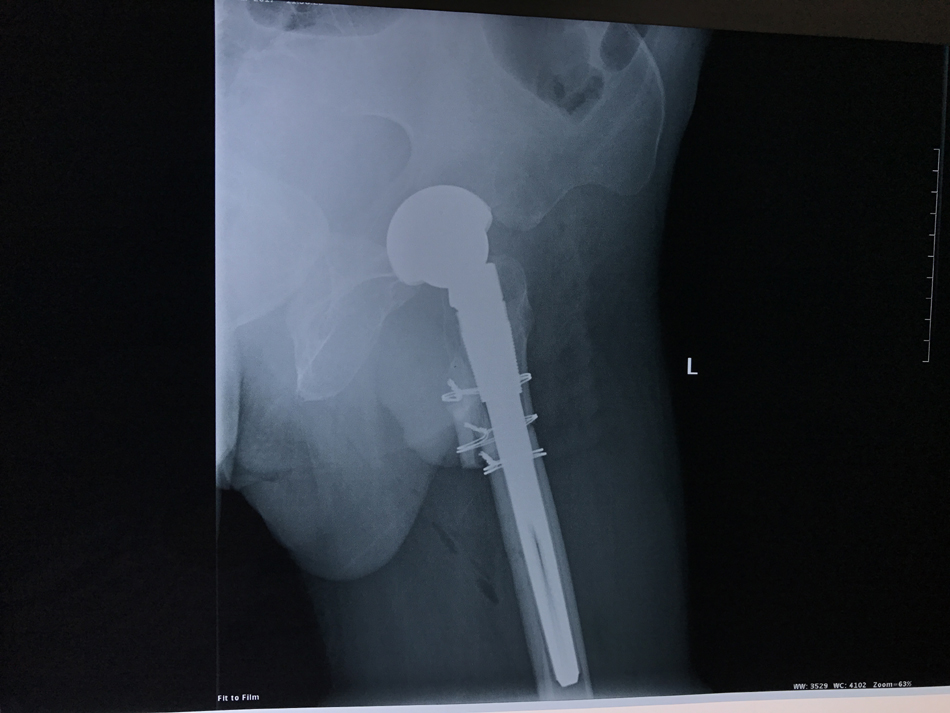

近日,关节与显微修复外科利用S-ROM假体结合股骨粗隆下截骨行人工全髋关节置换成功治疗一例CroweⅣ型先天性髋关节脱位。该患者男性,55岁,左髋疼痛伴活动受限30年,加重5天。术前射片诊断为左侧先天性髋关节脱位(CroweⅣ型),左下肢较右下肢短缩约4cm。术前,胡孔足副主任医师结合患者病史,体检及辅助检查,反复讨论,制定了精细的手术方案,手术顺利,术后患者第一天即可下地行走,稳定性良好,双下肢等长,极好地减轻患者疼痛,矫正畸形,提高了患者生活质量。

先天性髋关节脱位,又称发育性髋关节脱位,是临床常见的髋关节疾病,如果幼年时期没有得到有效治疗,发展到晚期可出现髋部严重的疼痛和关节功能障碍。其中CroweⅣ型先天性髋关节脱位是最严重的髋关节脱位,畸形严重,手术难度极大,是关节外科公认的人工关节置换最顶尖难度的手术。手术需要精细地重建髋臼,恢复髋关节旋转中心,同时需行股骨缩短截骨,减轻软组织张力,避免血管神经损伤。还要选择合适的假体,从而获得良好的畸形矫正和假体复位。关节置换风险高,并发症多。粗隆下截骨可以保留臀中肌的附丽点,保留了股骨干骺端的松质骨,股骨短缩的程度不受限制,有利于维持股骨正常的解剖结构,为假体提供更大的抗旋转力。采用组配式的设计人工关节假体,可提供抗旋转稳定性,可对骨块的远近端起到良好的压配作用,同时可以灵活调整股骨前倾角。通过多学科有效合作,手术顺利完成,术后康复良好。